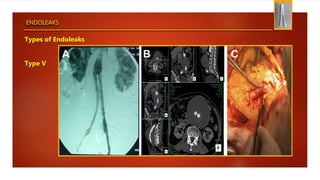

Types of Endoleaks

Type V

ENDOLEAKS